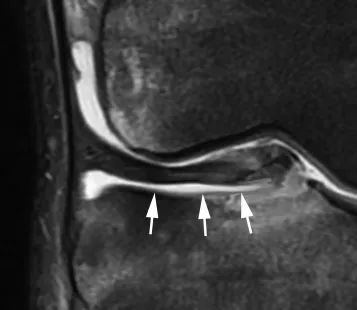

Они приводят к смещению верхнего мениска на 5 мм от заднего края пластины большеберцовой кости на сагиттальных изображениях (рис. 11) или проникновению жидкости между основанием мениска и плоскостью суставной капсулы.

Рисунок 11. Отслойка заднего рога мениска.Сагиттальный вид плотности протонов.Отделившийся мениск смещен кпереди.Имеется большая область гиперинтенсивности (*) между основанием мениска и задней капсулой (стрелка).